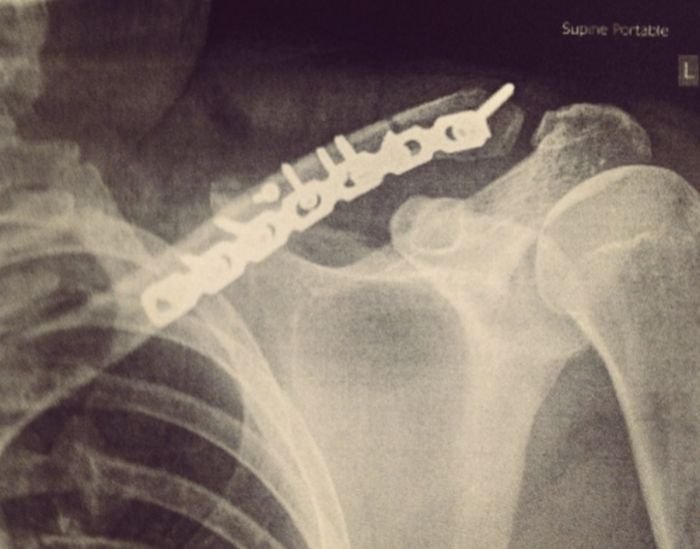

Нэгэн залуу 2015 онд цанаар гулгаж байхдаа хүндхэн бэртэл эгэм болон хавиргаа хугалж байжээ. Харин энэ бэртлийн дараа эгэм хавиар нь хөндүүр байсаар л байжээ.

Тиймээс саяхан рентген зургаа авахуултал ийм төмөр байсан аж. Харин үүнийгээ дурсгал болгон өөртөө бөгж хийлгэн хадгалжээ.